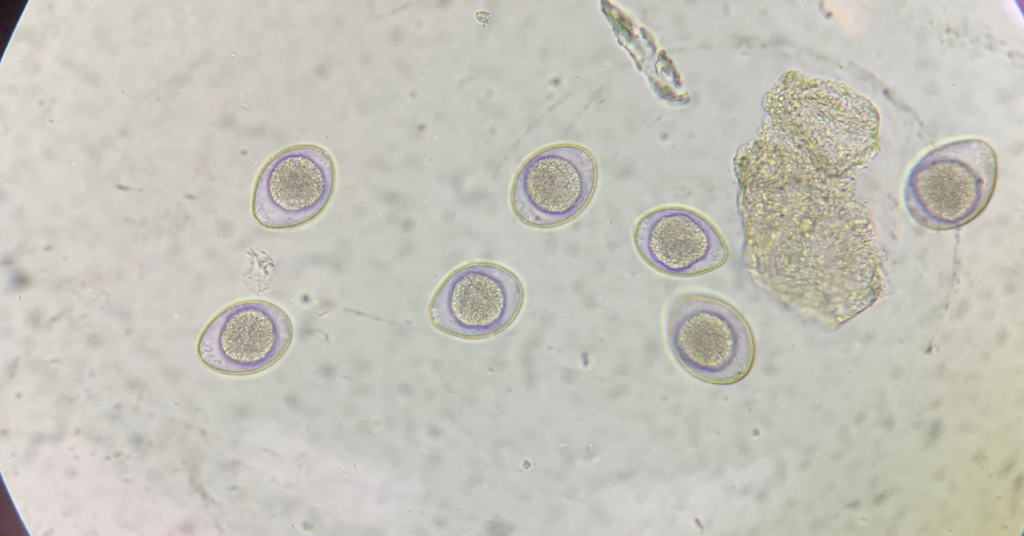

生活を変えてから約3ヶ月弱が経ったある日。私はAmazonで購入した「市販の精子チェッカー」を手に、自室のデスクに向かっていました。正直、期待はしていませんでした。過去、不妊クリニックの顕微鏡で何度も「精子ゼロ」の結果を見てきたからです。

しかし、スマホのレンズ越しにプレパラートを覗き込んだその瞬間から、私と精子の「格闘」が始まりました。

市販の簡易的なキットということもあり、少しでも光の加減が悪いと何も見えません。ピントを合わせるのも一苦労です。 「やっぱりいないのか……」と諦めかけ、デスクの上でレンズを微調整し続けること、実に1時間。

静まり返った部屋で、根気強く画面を探し続けたその時。 スマホの画面を、白く、小さな、しかし力強く動く物体が横切ったのです。

「いる……! 生きている精子がいる!」

たった数匹だったかもしれません。でも、あの日、無精子症と言われた私にとって、その一匹は絶望を打ち破る巨大な光でした。泣きながら妻を呼び、二人で震えながら、何度も画面を拡大しました。あんなに遠くに感じていた「パパになる」という未来が、今、自分のデスクの上にある。その震えるような感動は、一生忘れることができません。